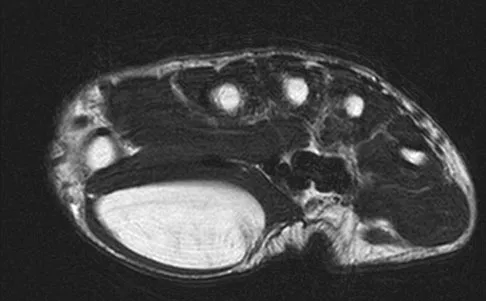

A 17-year-old man sustained a 5-mm laceration on the lateral aspect of the hindfoot while working on a farm. Examination in the emergency department revealed no fractures. Twenty-four hours later, he returns to the emergency department with increasing foot pain. Thin brown drainage is seen emanating from the wound. He has a temperature of 102.0 degrees F (38.9 degrees C), a pulse rate of 120, and a blood pressure of 80/40 mm Hg. Examination of the foot reveals diffuse swelling, ecchymosis, tenderness, and crepitus with palpation. Current radiographs are shown in Figures 40a and 40b. Management should now consist of

Explanation

The mechanism and environment in which the injury occurred, the clinical picture, and the radiographic findings of gas in the tissues suggest an anaerobic Gram-positive bacterial infection. This can be a life- and limb-threatening infection. Treatment should consist of wide debridement of all devitalized tissue, and intravenous antibiotics should be started. Wounds should be left open to allow bacterial effluent and increase oxygen tension in the wound. Hyperbaric oxygen may be used as an adjuvant but is no substitute for debridement. Pellegrini VD, Reid JS, Evarts CM: Complications, in Rockwood CA, Green DP, Bucholz RW, et al (eds): Rockwood and Green's Fractures in Adults, ed 4. Philadelphia, PA, Lippincott-Raven, 1996, vol 1, pp 458-463.